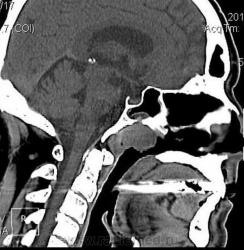

Мужчина 67 лет, обратился к отоларингологу с жалобами на заложенность носа, сосудосуживающие капли - без эффекта. Болен около месяца. На осмотре ЛОР-врач выявил образование свода носоглотки, направил на КТ.

Плотность 37-45 ед.Н, размеры 2х2х2.5 см. Бугристый контур, прилежит к нижнему контуру основной кости с ее деструкцией и прорастанием в основную пазуху. Диагноз не вызвал сомнений, решено контрастирование не выполнять. Направлен в областной онкодиспансер, ждем заключения.

Первые три - первичные аксиальные срезы в "мягкотканном" и "костном" окне в зоне интереса.